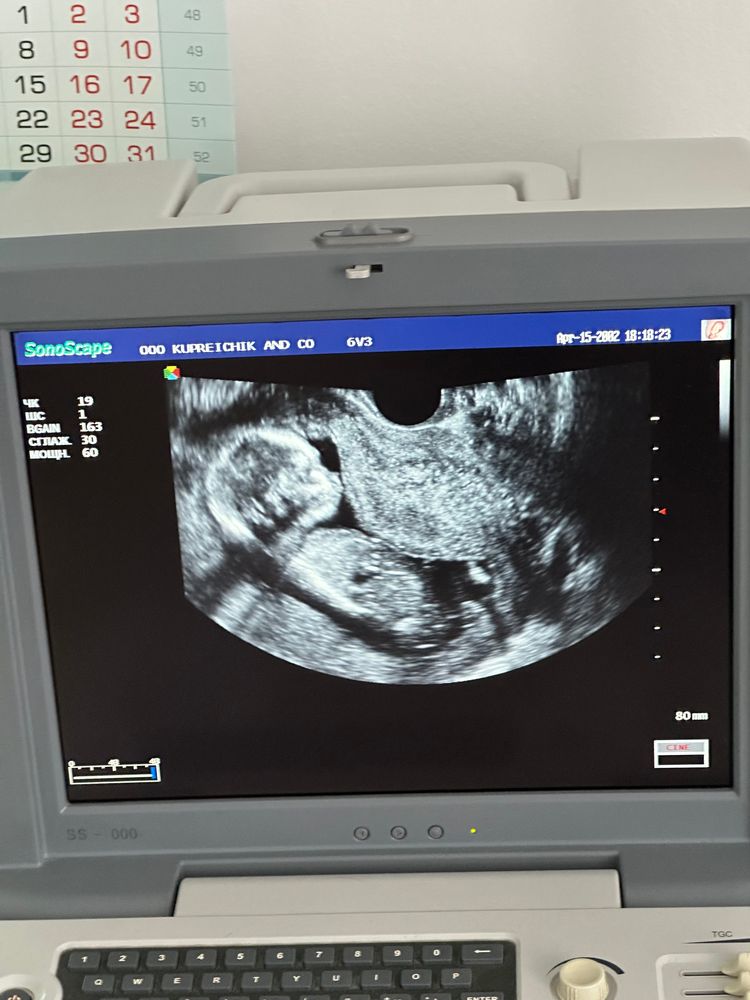

Мальчик или Девочка??,

может кто-нибудь поймет мальчик или девочка? 😅😄срок почти 16 недель. То мальчик говорят, то девочка🙈

не очень удачное фото, но если глядя на то место, где половой бугорок , склоняюсь в мальчишке, вверх немного торчит

Софья,

Sia Forest, у меня вот так на узи в 14,6 недель